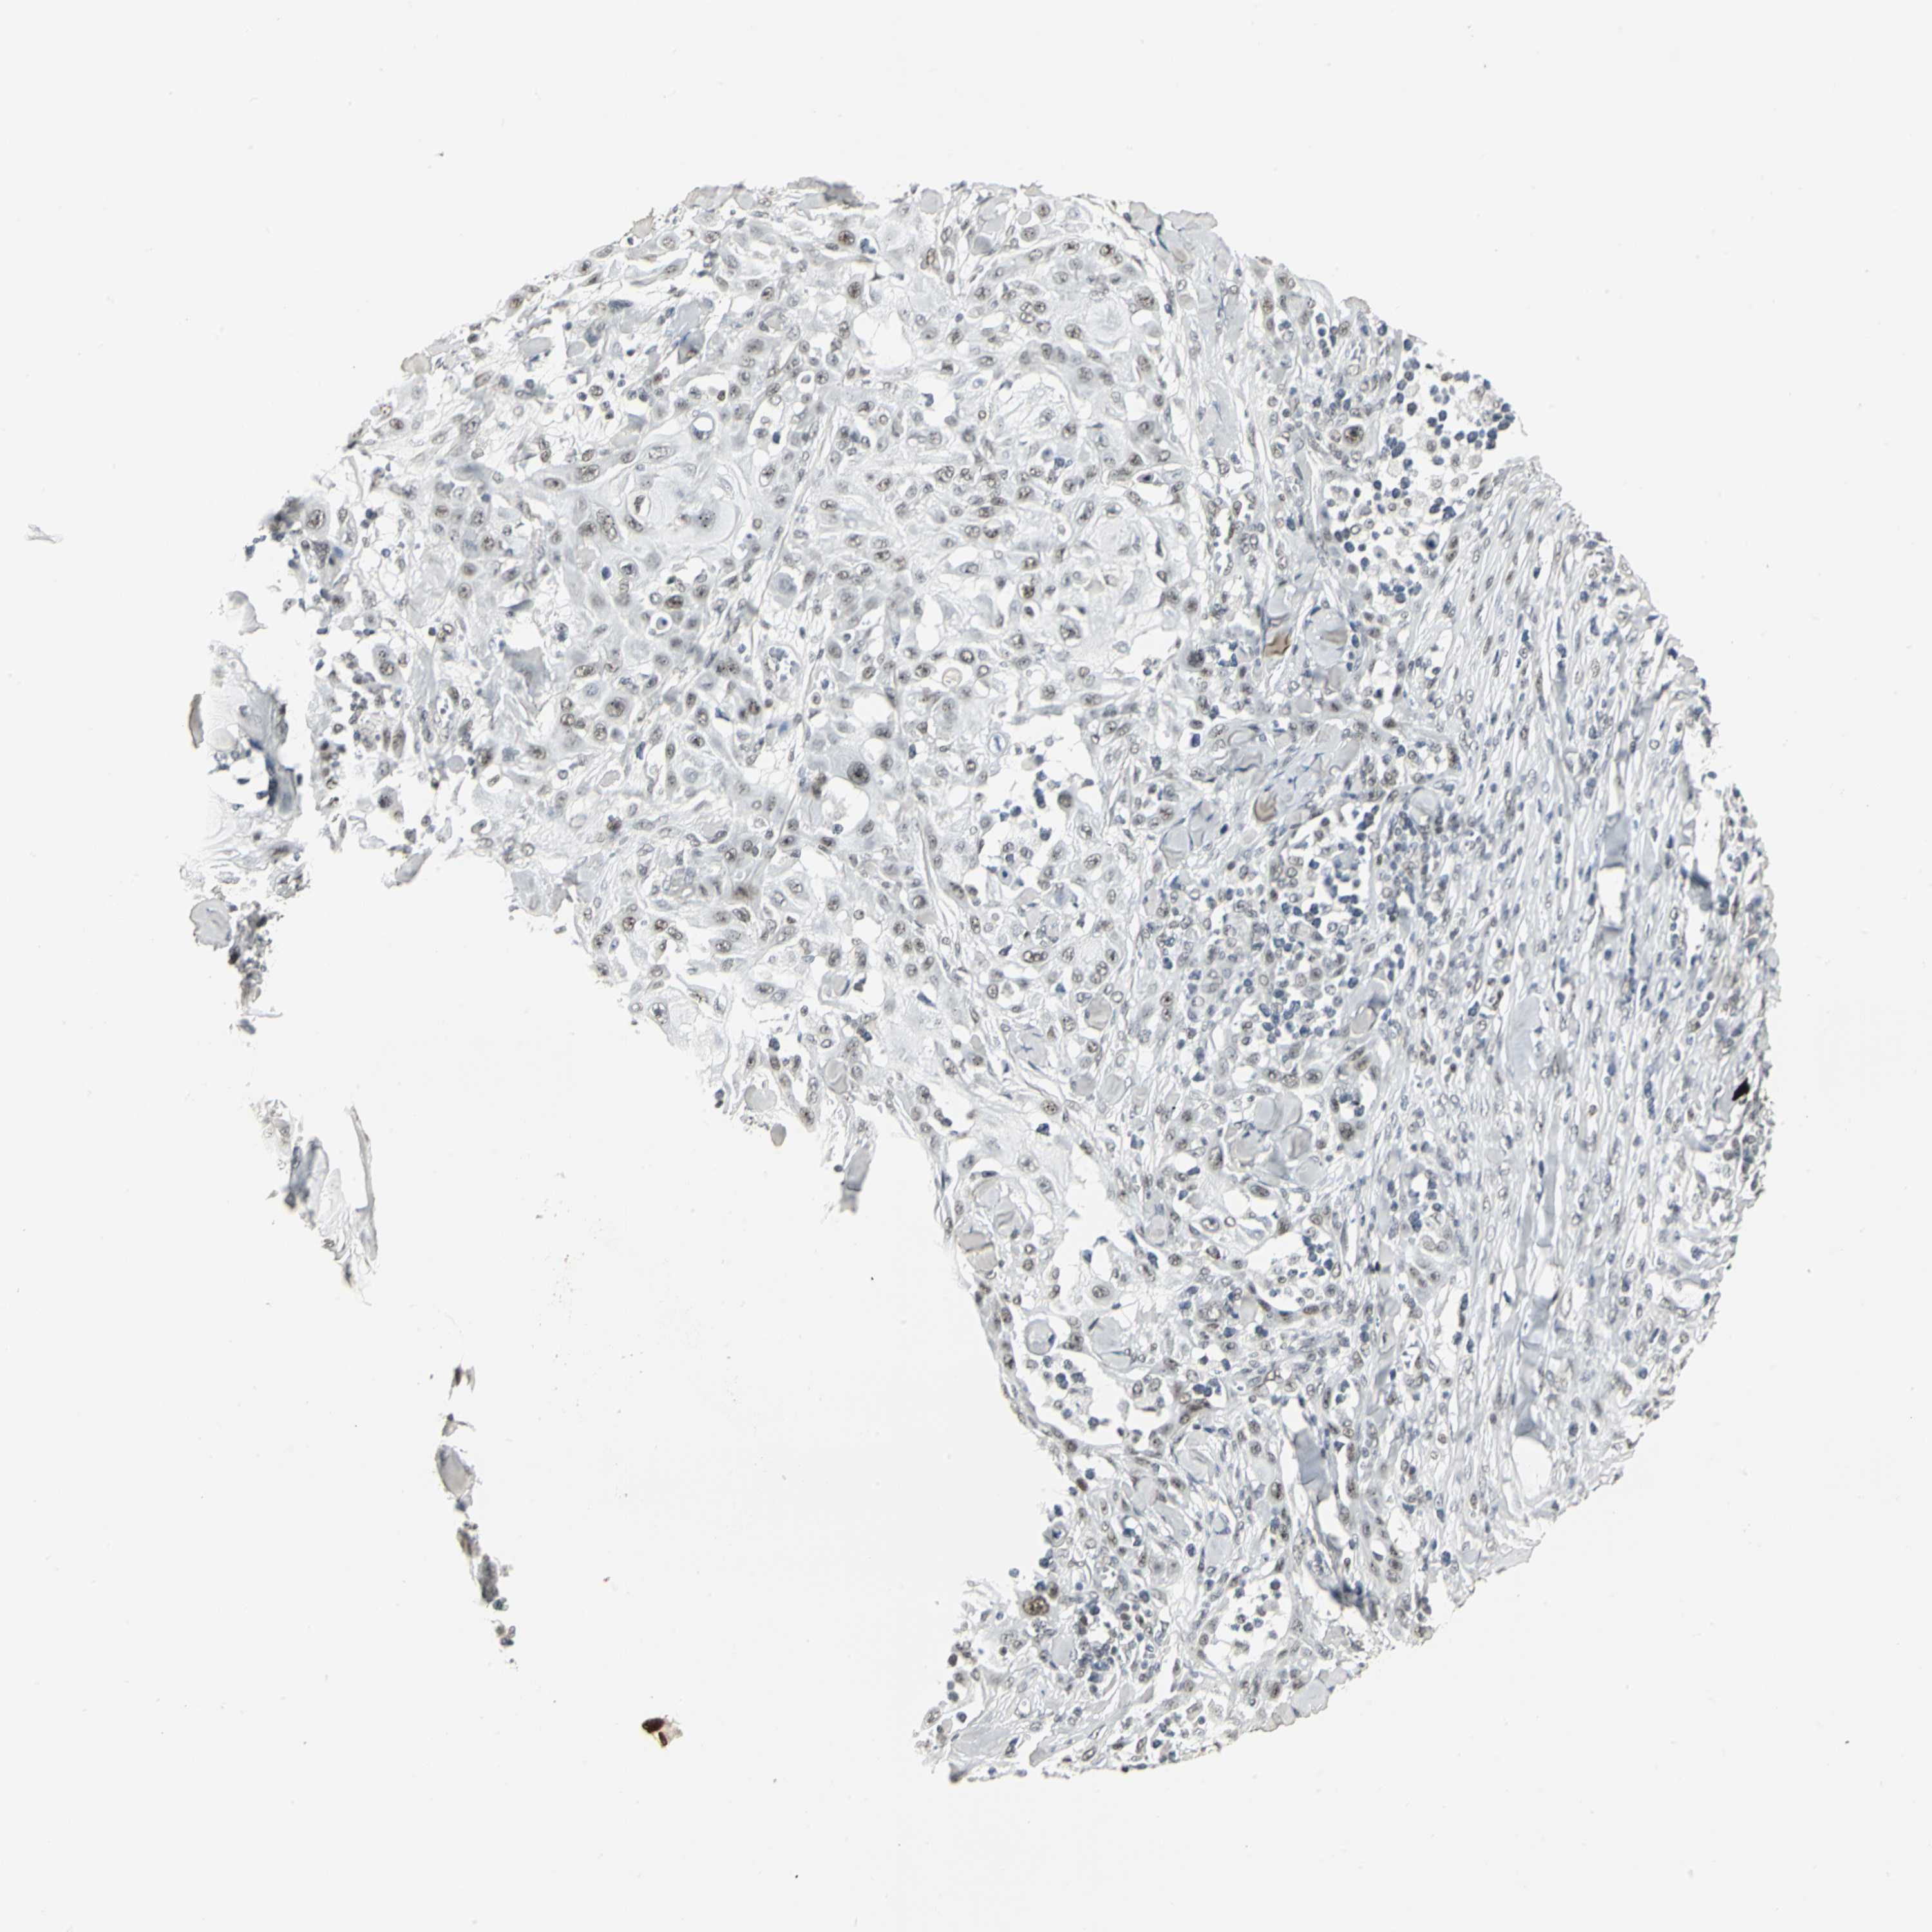

CANCER SKIN CANCER Show tissue menu

SKIN CANCER - Protein expressioni

A mouse-over function shows sample information and annotation data. Click on an image to view it in a full screen mode. Samples can be filtered based on level of antibody staining by selecting one or several of the following categories: high, medium, low and not detected. The assay and annotation is described here.

Each image is clickable and will lead to virtual microscopy that enables deeper exploration of all samples and also displays staining intensity scores, fraction scores and subcellular localization as well as patient and tissue information for each sample.

Antibody HPA004902

Antibody CAB001973

Squamous cell carcinoma, NOS

Basal cell carcinoma